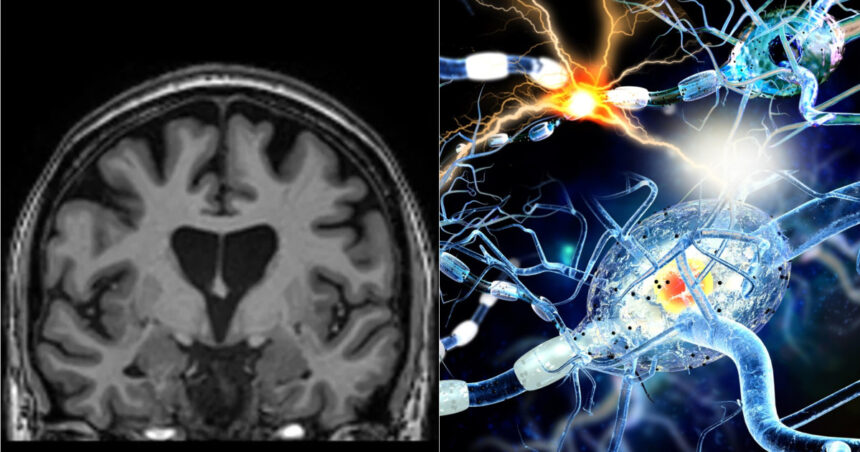

Un nou studiu realizat de o echipă de la Universitatea Griffith sugerează că infecţia cu SARS-CoV-2 poate provoca modificări măsurabile în creier, chiar și la persoanele care se consideră complet vindecate și nu mai prezintă simptome. Cercetarea a folosit tehnici avansate de rezonanță magnetică (RMN) pentru a evalua sănătatea creierului la indivizi care au avut Covid-19, rezultatele fiind comparate cu cele ale participanților care nu au fost infectați.

Analiza imaginilor RMN a arătat semne clare că o infecție anterioară cu SARS-CoV-2 poate lăsa urme detectabile în creier, inclusiv în absența simptomelor persistente. Aceasta sugerează că efectele virusului pot continua dincolo de faza acută a bolii, fără a fi neapărat evidente clinic. Echipa a utilizat imagistică multimodală pentru a examina atât substanța cenușie, cât și substanța albă, regiuni esențiale pentru memorie și funcții cognitive.

Dr. Kiran Thapaliya, autorul principal al studiului, a declarat că investigațiile RMN au evidențiat modificări semnificative ale substanțelor chimice din creier, ale intensității semnalului și ale structurii țesutului cerebral. Aceste modificări au fost observate nu doar la persoanele cu sindrom post-Covid, ci și la cele considerate complet recuperate. De asemenea, gradul de modificare a țesutului cerebral a fost asociat cu severitatea simptomelor, susținând ipoteza unor efecte persistente asupra sănătății creierului.

Rezultatele acestui studiu adaugă noi dovezi cercetărilor anterioare care sugerează că virusul SARS-CoV-2 poate persista în creier și poate deregla activitatea neuronilor. Alte studii au indicat că infecția ar putea genera modificări similare celor observate în boala Alzheimer. Autorii studiului subliniază că noile date oferă indicii importante despre modul în care SARS-CoV-2 afectează sistemul nervos central și contribuie la înțelegerea problemelor cognitive, precum dificultățile de memorie și concentrare, ce pot apărea atât la scurt timp după infecție, cât și la luni sau ani distanță.